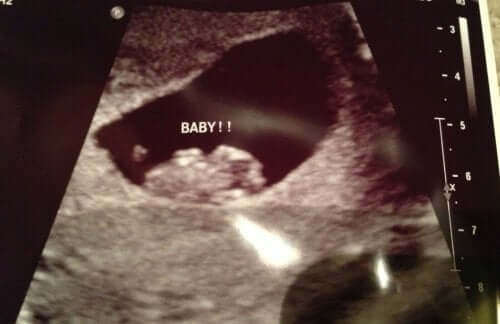

Esami in gravidanza

L'attenzione prenatale è fondamentale affinché tu e il tuo bebè viviate questo processo nel migliore dei modi: in salute e benessere. Questo è il nostro obiettivo e per favorirlo mettiamo a tua disposizione adeguati dati su cure, esami e dinamiche da seguire ogni trimestre. Ogni mamma merita di avere una gravidanza sana e felice.